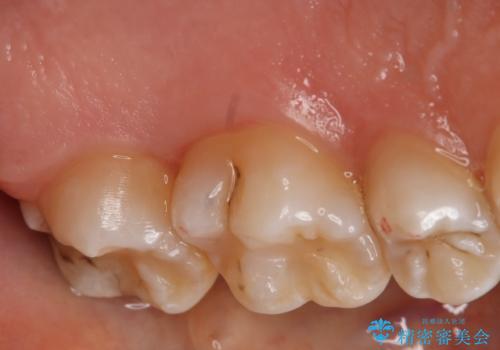

奥歯を治療したい フルジルコニアクラウン

- 左上7番の虫歯治療を主訴に来院された患者様です。

虫歯の範囲が広かったので切削量・形態を考慮し、セラミッククラウンでの治療を計画しました。

- 99000円(フルジルコニアクラウン+仮歯)費用は治療当時の料金となります